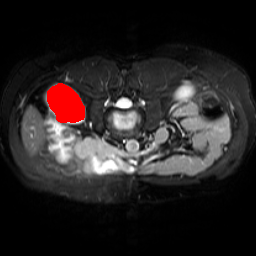

In order to assess the performance of the proposed method, we compare the performance of the proposed model with excellent models in recent years. Table 1 and Table 2 shows the comparison results of different models in setting1, while Table 3 and Table 4 shows the comparison results of different models in setting2 on the data set in recent years. PANet[25] is the most widely influential few-shot model in the field of few-shot image segmentation on natural images. SENet [18] is the first few-shot segmentation model proposed for medical images. SSL-ALPNet[19] introduced the milestone of using superpixel self-supervision to train few-shot medical image models. RPNet[29] is a supervised method with a recursive mask optimization module to iteratively optimize the segmentation mask, [27] adapt it into the same self-supervision learning framework and applies setting1 to it and denoted as SSL-RPNet; CRAPNet[27] is the latest SOTA model for 2023. Compared with CRAPNet, our method outperforms most of the state-of-the-art models and only slightly outperforms CRAPNet. Figures 3 and 4 show examples of the model’s segmentation predictions on different datasets, respectively; The first row is the support map, the second row is the label map, and the third row is the segmentation prediction of the model.